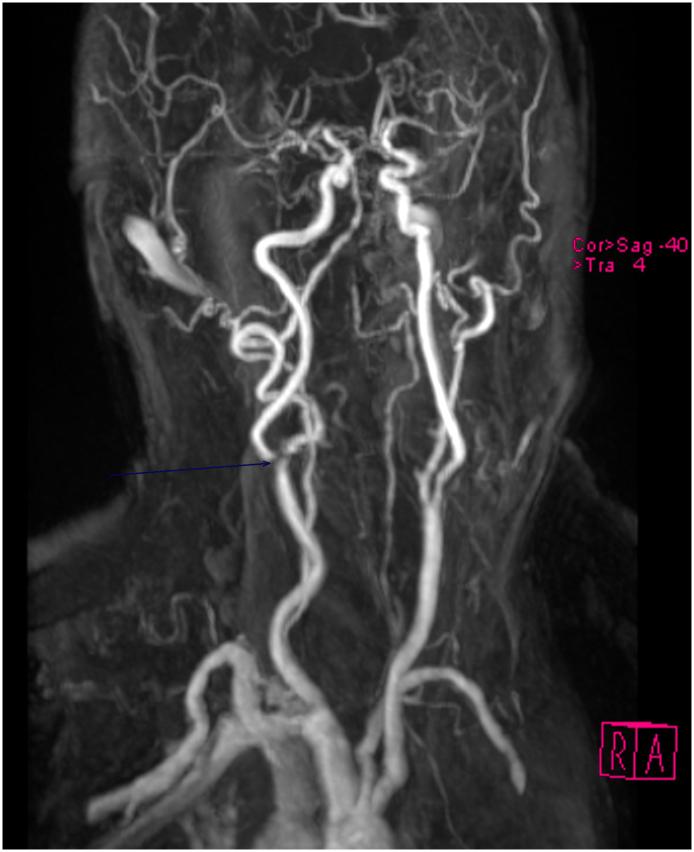

Takotsubo syndrome (TTS) is a transient transient left ventricular dysfunction, predominantly affecting elderly women and often preceded by emotional or physical stress. TTS may be the cause as well as the consequence of stroke. We report a 82-years old female with a history of long-standing untreated arterial hypertension who was hospitalized because of a left-sided tongue paralysis and dysarthria. Cerebral magnetic resonance imaging showed ischemic lesions in the territory of the right middle cerebral artery affecting the capsula interna and gyrus praecentralis. The carotid and cerebral arteries showed extensive atherosclerotic wall irregularities, a high-grade stenosis of the M1-segment of the right middle cerebral artery and a 60% stenosis of the internal carotid artery at its origin. Elevated creatine-kinase and Pro-brain-natriuretic peptide levels and development of new ischemic signs in the electrocardiogram suggested myocardial infarction, although the patient did not complain about cardiac symptoms. Echocardiography showed apical ballooning which resolved during the following days. The patient refused coronary angiography why the diagnosis of TTS was not completely established. However, normalization of echocardiogram and ECG were indicative for TTS. TTS has to be considered in stroke patients, irrespective of their etiology. Since patients often do not report typical symptoms or may even be asymptomatic, TTS can be overlooked. If the ECG in stroke patients shows signs of myocardial ischemia, troponin and BNP levels should be measured whose ratio may even help to differentiate between TTS and myocardial infarction. Echocardiography, coronary angiography and follow-up investigations are needed to confirm the diagnosis of TTS.